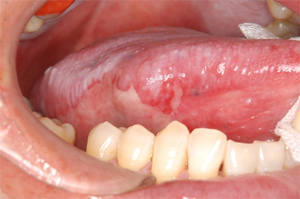

これらの治療により、口腔粘膜が赤く腫れ気味になり、それとともに表面が少しでこぼことなり、粘膜の一部がはがれて潰瘍(かいよう)ができる場合もあります。

抗がん剤と放射線の同時併用した場合にはさらに、口内炎の症状が強く、また長期間続きます。口内炎には強い痛みが伴います。特に口の粘膜からのどの粘膜に口内炎が広がると食べ物ばかりでなく、水などの液体をとることもつらくなってきます。この状態が長期間続くと、栄養不足や脱水状態になります。